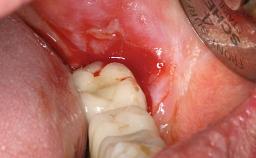

A 77-year-old male patient was referred for the management of frequent and repeated acrylic fracture of his existing mandibular fixed full-arch implant-supported metal/acrylic prosthesis. He also complained about softtissue soreness and the lack of retention and stability of his maxillary removable partial metal/acrylic prosthesis. Both prostheses had been delivered two years previously as part of his full-mouth rehabilitation (caries, tooth wear, tooth fracture). His medical history revealed high blood pressure, controlled with the use of antihypertensive medication.

Periodontal Status History of periodontitis or genetic predisposition

Oral Hygiene and Compliance Insufficient